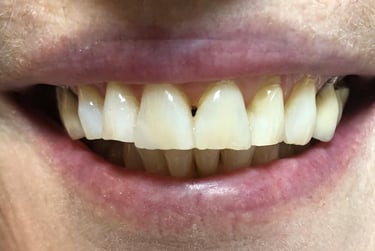

Aspecto Clínico Final - Fotografias originais — nenhuma contém retoques — A cor dos dentes é escolhida de acordo com o gosto e a preferência estética de cada paciente.

Depois

Depois - Restauração em resina associada ao clareamento dental.